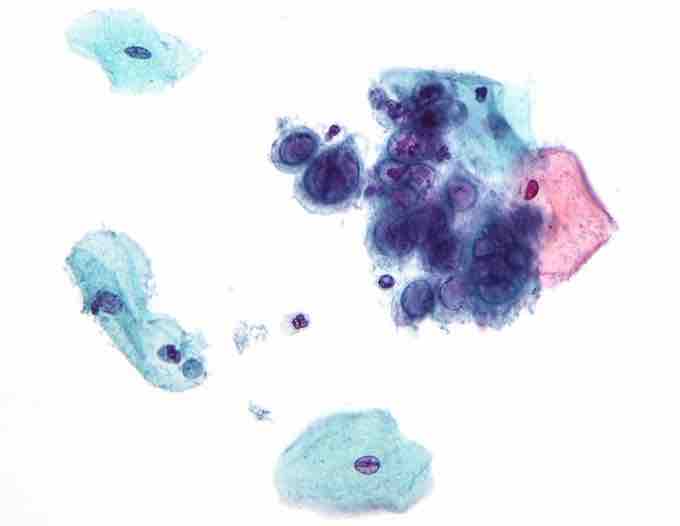

Micrograph of a pap test showing changes (upper-right of image) associated with Herpes Simplex Virus, a TORCH infection.

Herpes Simplex Virus

- H – Herpes simplex virus